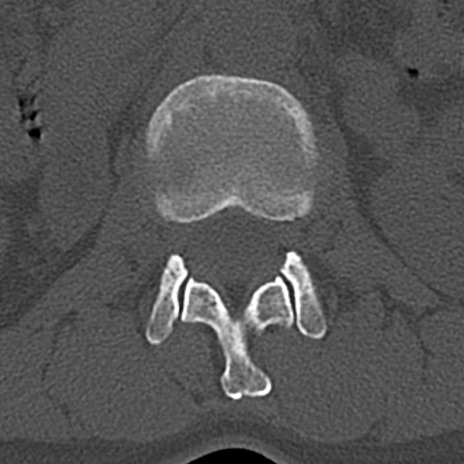

腰椎CT

横断像と矢状断像